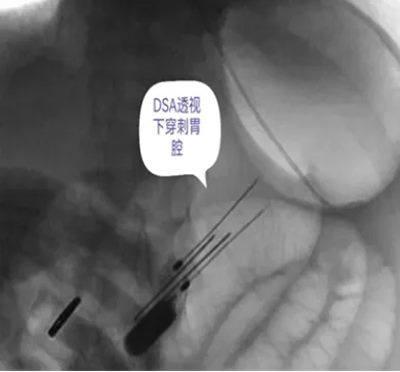

DSA引导下经皮胃造瘘术,是在数字减影血管造影(DSA)这个“透视眼”的实时可视化导航下,于患者腹壁上建立一个仅 3-5毫米 的微小穿刺点。通过这个“针眼”,医生精准地将一根营养管直接置入胃部,建立起一条直达的营养通道。

整个过程就像一次精准的“导航穿刺”,全程操作便捷、创伤小,却能完美替代传统的鼻饲管,为患者提供长期、稳定、安全的营养支持。